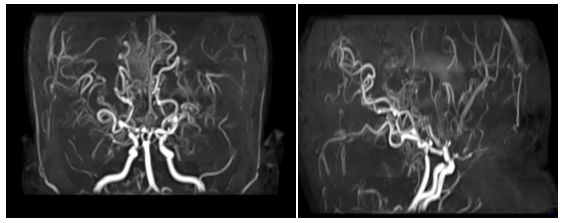

This is a 27year-old woman who has been known to have had sickle cell anemia since childhood, and who brutally presented a picture of meningeal haemorrhage caused by severe headache, vomiting. The clinical examination finds a patient subbérile subfebrile with a stiff neck. An MRI performed urgently in the three planes of space in weighted sequences T1, T2 FLAIR and angio-RM arterial. It reveals intra-ventricular haemorrhage as well as fine serpiginous vascular structures in the sylvian valleys and peri-mesencephalic. MRA shows the absence of the supraclinoid segments of the internal carotids with development of a fine cortical anastomotic network and at the Willis polygon Figure 1 & 2.

Figure 2 Arterial Angio-MRI in flight time: absence of visualization of the supraclinoid segments of the internal carotids as well as the proximal portions of the anterior and middle cerebral. A cortical anastomotic network is located at the base and visualization of the distal segments of the cerebral arteries where the flow is slowed down.

This is a 16-year-old girl, followed for sickle cell anemia since the age of 2years, having an antecedent DALY at 5years of age; who presented a brutal presentation of alertness disorder with right hemicopra deficiency related to left posterior cerebral AVCI. An MRI performed urgently in the three planes of space in weighted sequences T1, T2 FLAIR and angio-RM arterial. It highlights an AVCI range of different age in the most recent is left carotid. The ARM shows the interruption of the two internal carotids at the level of their terminal segment C1, which are of reduced caliber in their intracavalous path with no individualization of the proximal segments of the 2 anterior and posterior cerebral arteries, a fine anastomotic network at the base "pseudomoya" Figure 3 & 4.

Figure 4 Arterial Angio-MRI: Interruption of the two internal carotid arteries in their C1 end segment, which are of reduced caliber in their intracavalous pathway with absence of individualization of the proximal segments of the 2 anterior and posterior cerebral arteries with evidence of a fine network at the "pseudomoya" base.

The biological assessment makes it possible to isolate the Moya Moya disease itself (Nishimoto's disease), for which by definition no etiology is found. Different etiologies produce the angiographic aspect of Moya Moya disease and are grouped under the term Moya Moya syndrome. The MRI associated with MRA, a non-invasive technique, has now become a first-line examination with a sensitivity and specificity of 70 to 100%. It allows the detection of parenchymal and vascular lesions. It shows signs of ischemia, haemorrhage and Moya Moya vessels. Realized in the three planes of space in weighted sequences T1, T2, FLAIR, T2*, diffusion with sequences ARM, as well as sequences T1 gadolinium.

The ARM sequences allow the study of the polygon of willis, of the carotid bifurcations, detects the aneurysms, but its resolution is still lower than that of the digitized angiography. It does not detect micro-aneurysmal lesions of less than 3 mm, may not objectify all small transdermal vessels and does not appreciate the extracranial vascular circulation necessary for surgical revascularization. Arteriography is the reference examination for diagnosis. It is essential for the assessment of the lesion. It allows to visualize intra- and extra-cranial vascularization.

Moya Moya is a rare chronic cerebral vascular disease, idiopathic or secondary, which is a not insignificant cause of stroke in sickle cell anemia. Diagnostic delay is frequent, due to its polymorphic symptomatology. AngioMR is currently the standard imaging for initial diagnosis and surveillance. Arteriography remains a gold standard for the diagnosis and precise lesional assessment of this pathology.